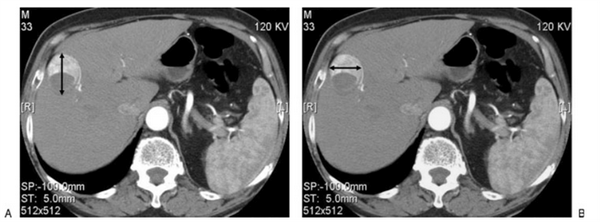

Применение mRECIST при оценке гепатоцеллюлярной карциномы. Оценка таргетного очага применительно только в артериальную фазу при компьютерной томографии (КТ). Согласно критериям RECIST идет подсчет суммы диаметров очагов. В дополнение согласно критериям mREСIST длинник очага оценивается в той части, что наиболее усилилась постконтрастно в артериальную фазу.

На верхних двух изображениях представлены после проведенного лечения (основная опухоль не представлена) первые повторные исследования в артериальной и венозной фазах, при которых выявлен очаг в размерах менее 1 см, что согласно критериям RECIST является не измеряемым. На вторых повторных исследованиях в артериальной и венозной фазах определяется очаг более 1 см с характерными признаками злокачественности (артериальной гиперваскуляризацией и венозным вымыванием), который является теперь измеряемым. В данном случае об прогрессировании заболевания после первого повторного исследования можно говорить только ретроспективно.